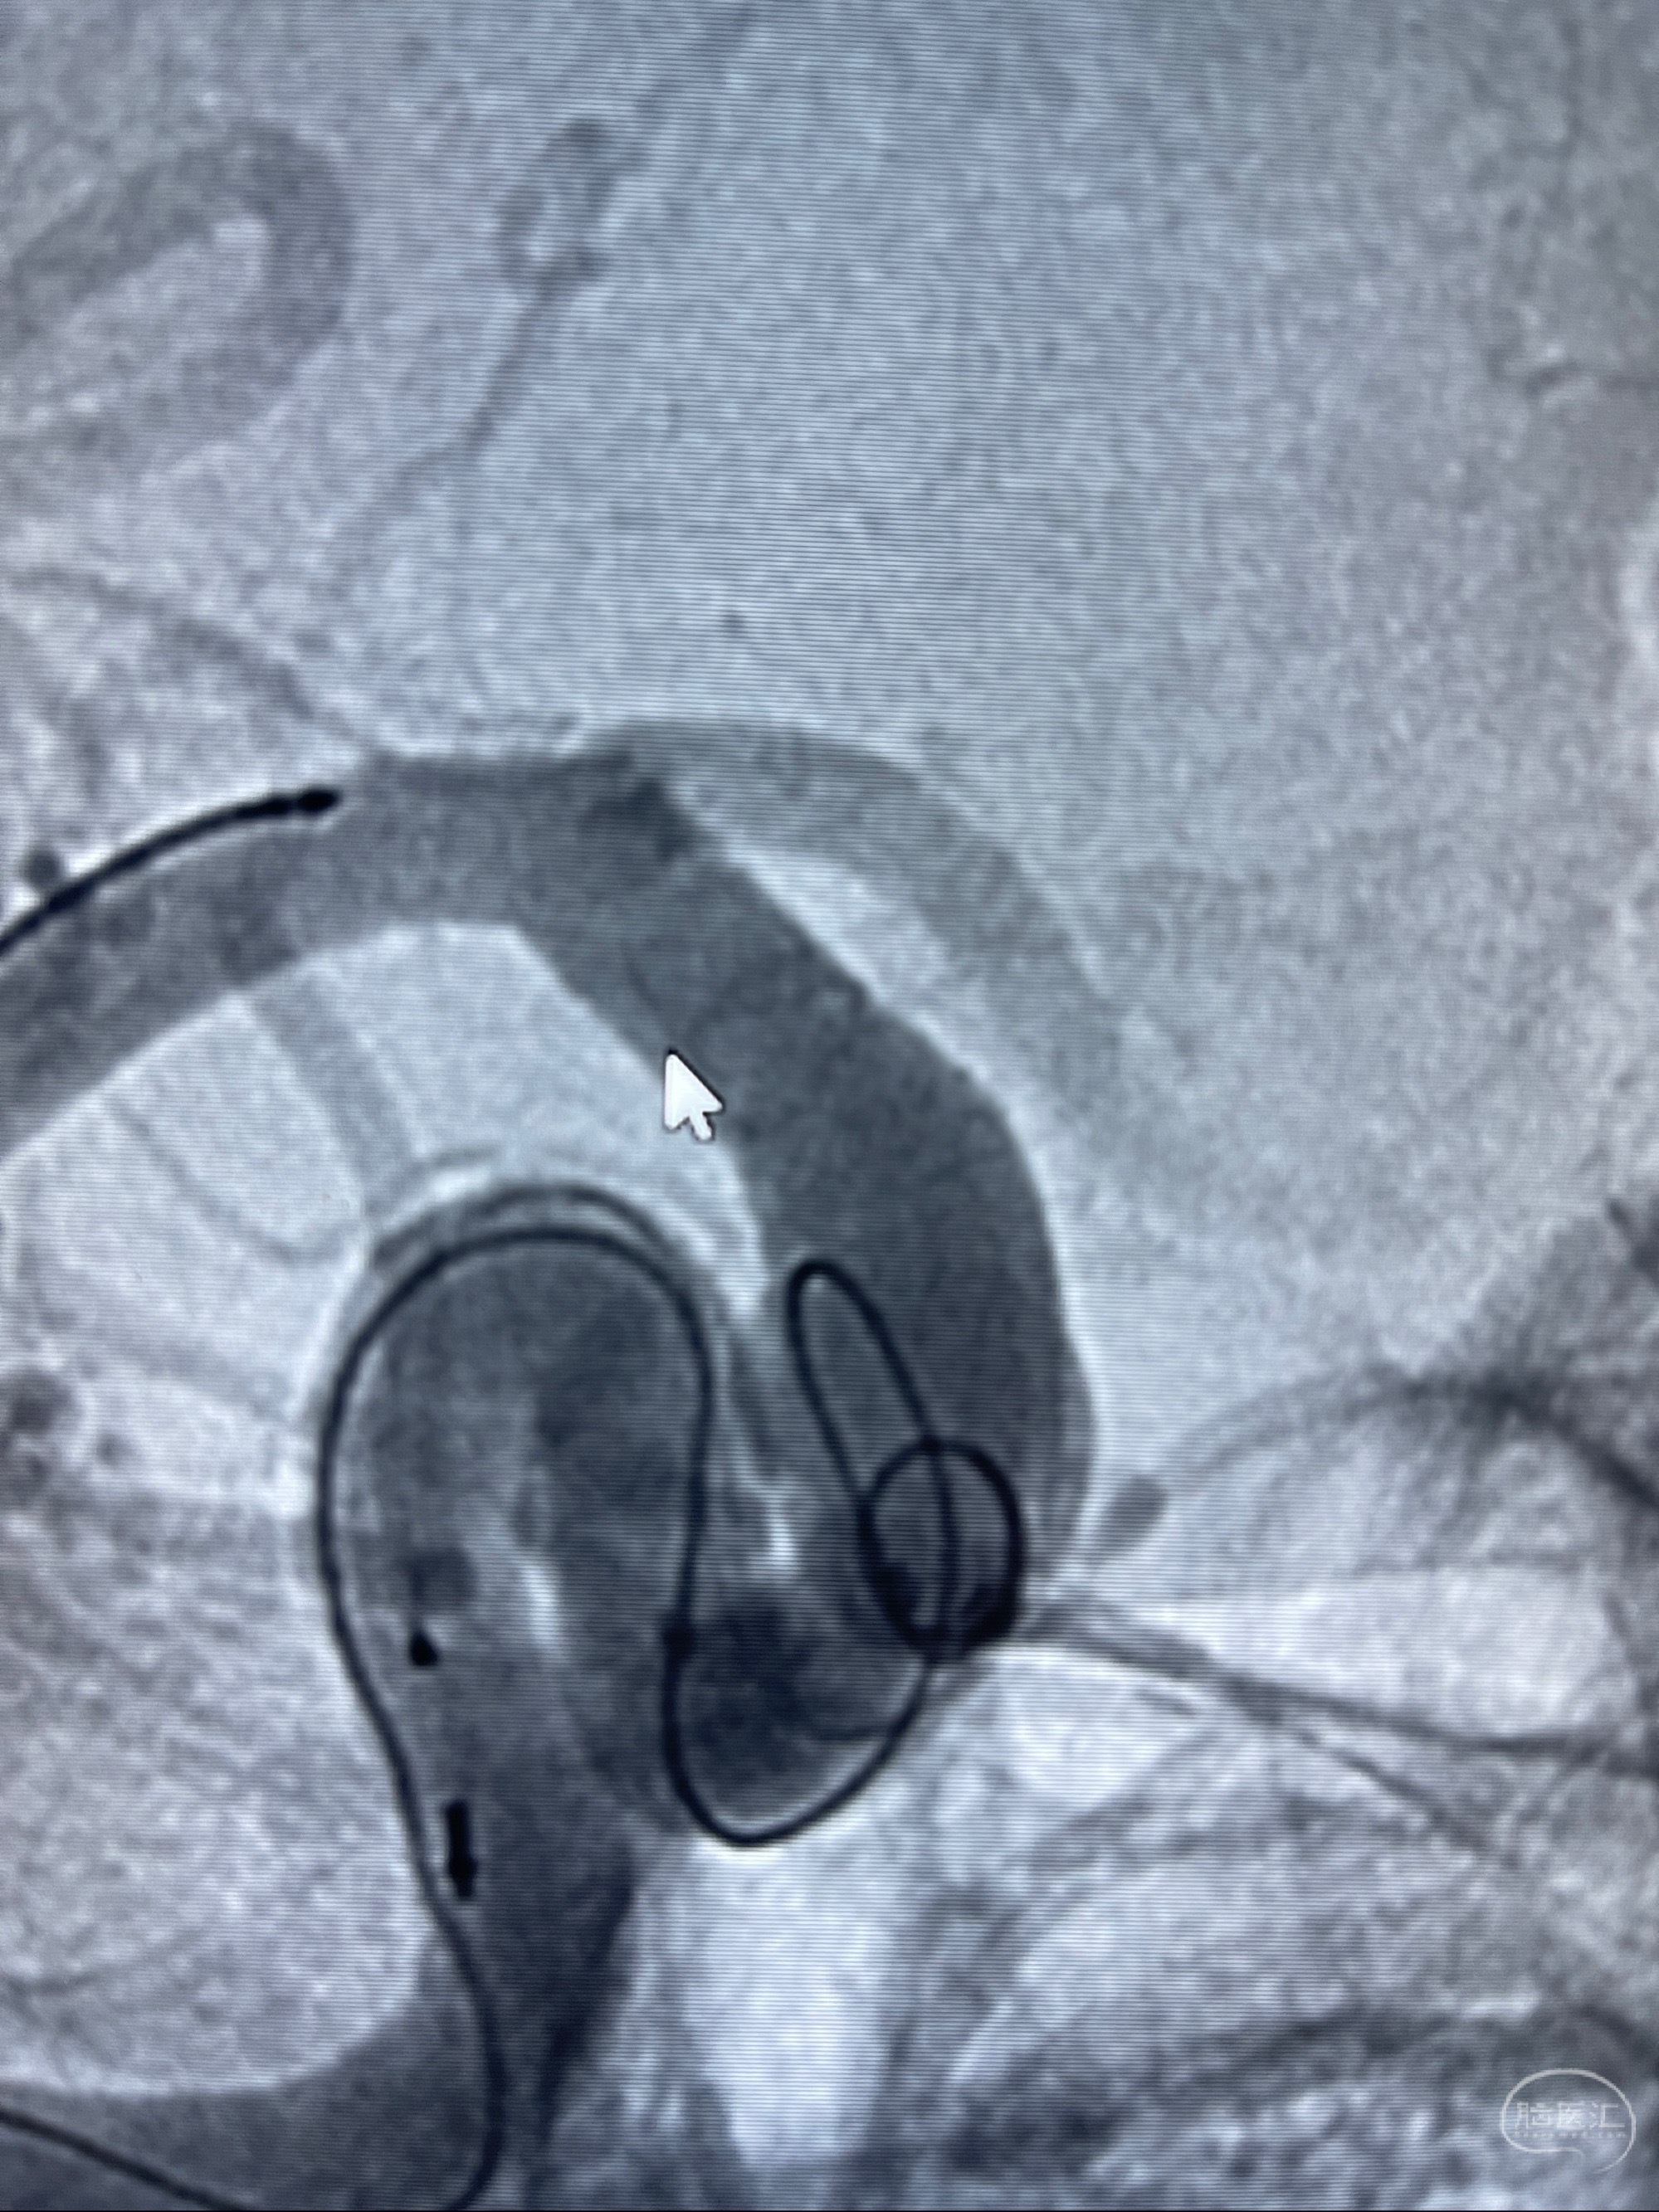

2023-08-01全麻下行双侧颈眼动脉瘤支架辅助栓塞

手术顺利,麻醉苏醒佳,遵嘱动作

术后即刻CT